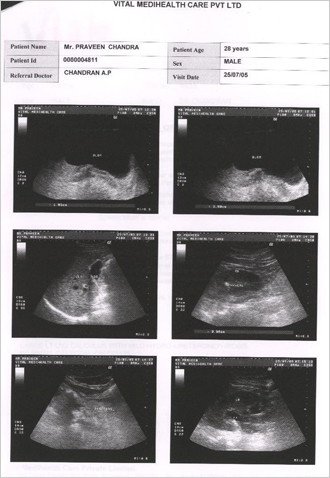

Condition of patient in beginning of Homoeopathic treatment for Kidney Calculus